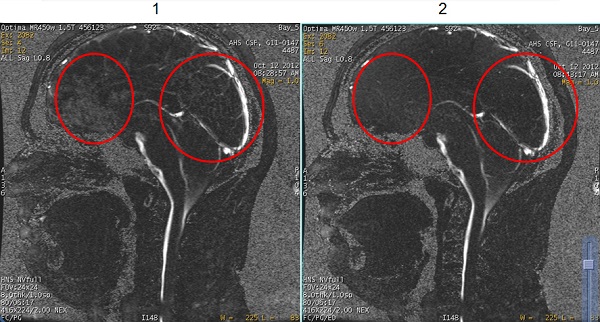

| 1 | Phase Contrast images acquired with Cine PC and SPGR Mode User CV set to 0, or Off. |

| 2 | Phase Contrast images acquired with Cine PC and SPGR Mode User CV set to 1, or On. Note the improved suppression of background tissue. |